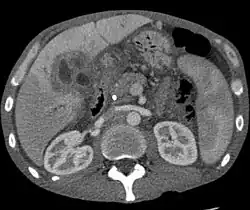

CT scan showing cholangiocarcinoma

Ultrasound of the liver and biliary tree is often used as the initial imaging modality in people with suspected obstructive jaundice.[50][51] Ultrasound can identify obstruction and ductal dilatation and, in some cases, may be sufficient to diagnose cholangiocarcinoma.[52] Computed tomography (CT) scanning may also play an important role in the diagnosis of cholangiocarcinoma.[53][54][55]